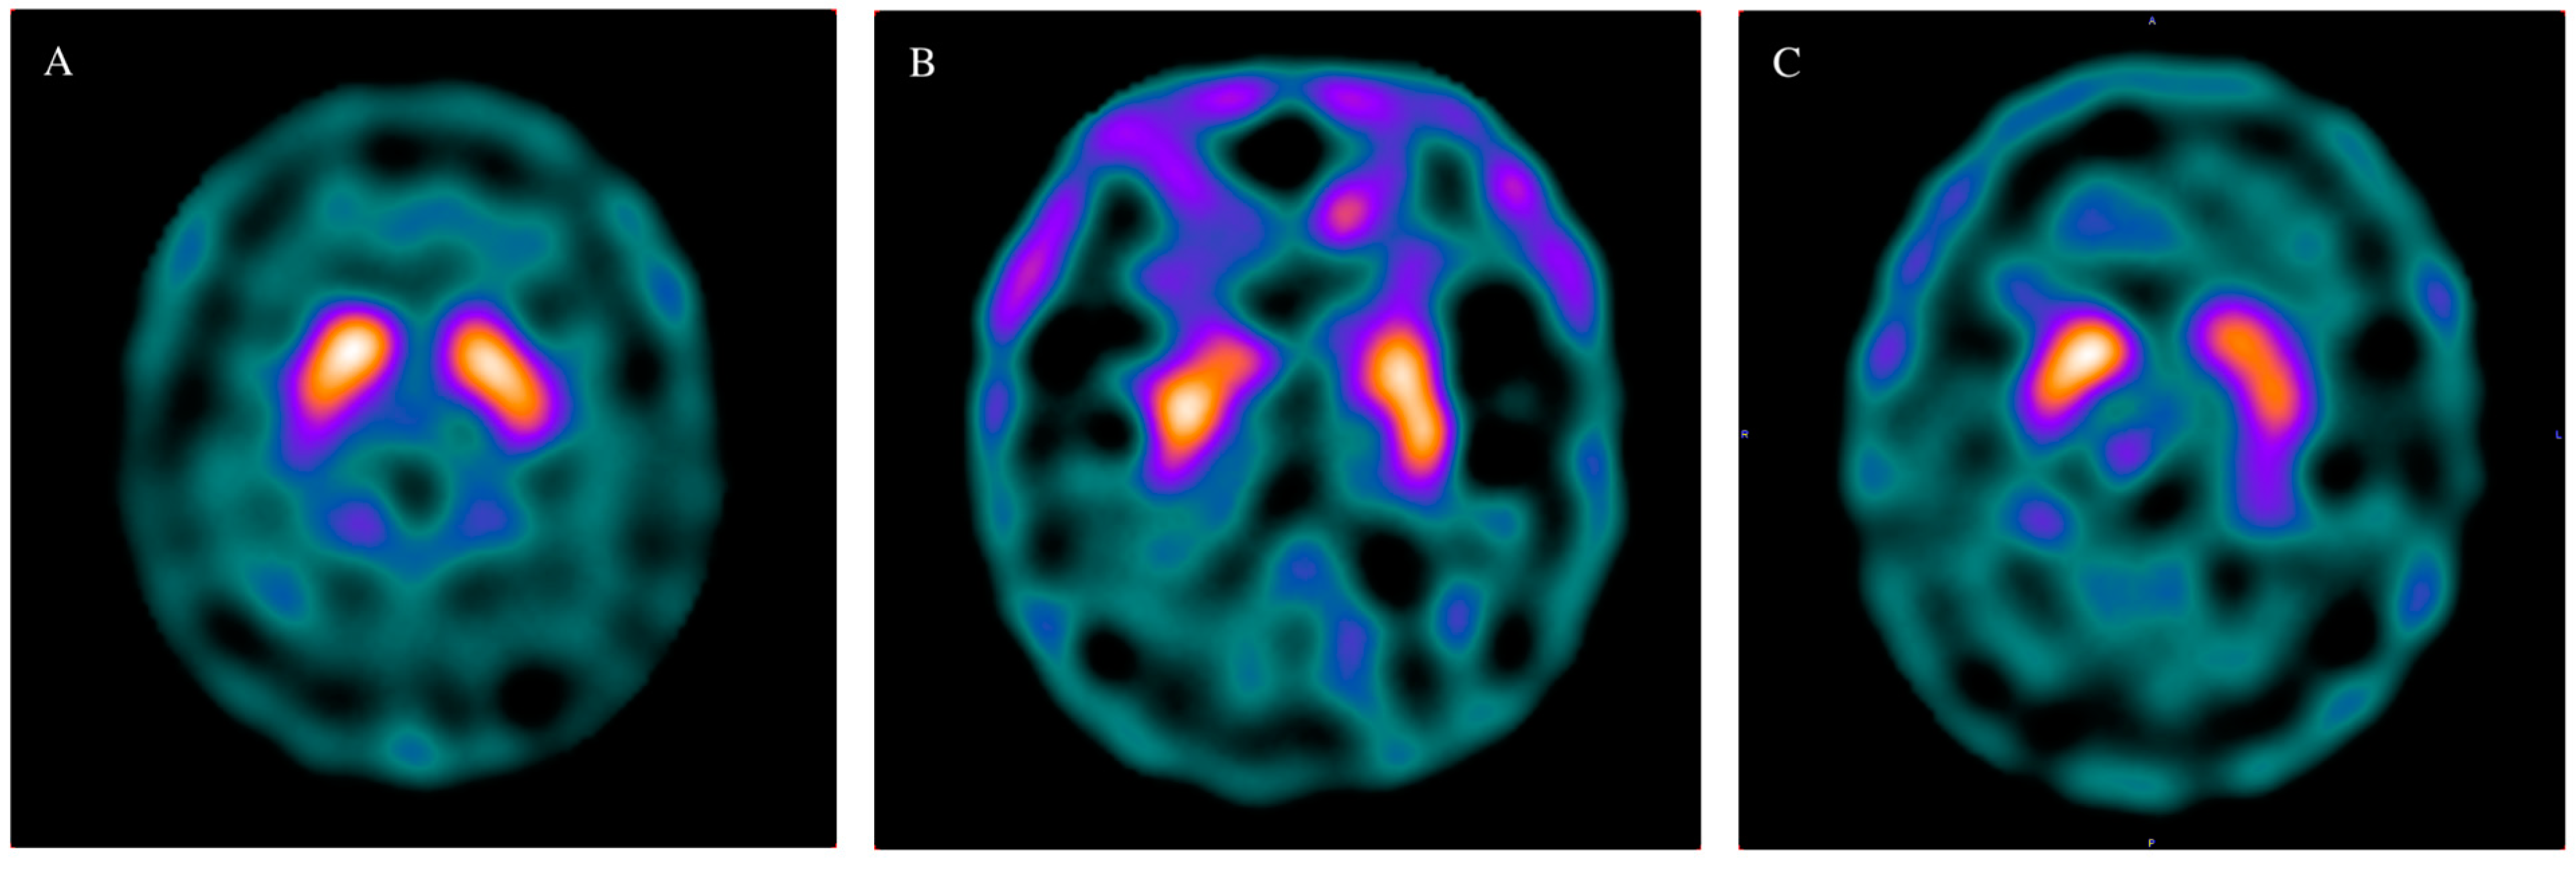

| Caudate, Right | 1.47 | 0.30 | 1.24 | 0.24 | 1.08 | 0.36 | 0.022 * |

| Caudate, Left | 1.46 | 0.30 | 1.32 | 0.22 | 1.11 | 0.43 | 0.078 |

| Putamen Right | 1.33 | 0.25 | 1.18 | 0.22 | 1.01 | 0.39 | 0.064 |

| Putamen Left | 1.35 | 0.31 | 1.20 | 0.18 | 1.01 | 0.41 | 0.071 |

| Basal ganglion, Right | 1.40 | 0.27 | 1.21 | 0.22 | 1.04 | 0.36 | 0.011 * |

| Basal ganglion, left | 1.41 | 0.30 | 1.26 | 0.20 | 1.06 | 0.41 | 0.065 |

| Total ratio | 1.40 | 0.28 | 1.24 | 0.20 | 1.05 | 0.38 | 0.046 * |